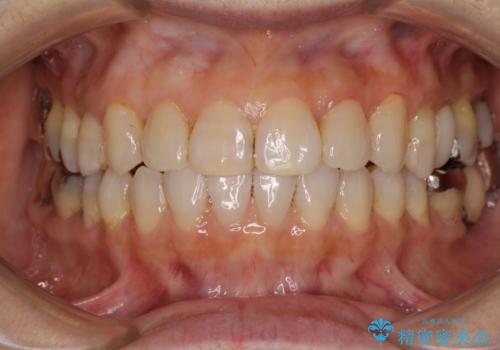

[ 前歯開咬 ] 前歯が噛んでいない マウスピース矯正治療

担当医 大元洋佑

![[ 前歯開咬 ] 前歯が噛んでいない マウスピース矯正治療の症例 治療前](https://seimitsushinbi.jp/wp/wp-content/uploads/2022/11/IMG_4669-500x350.jpg?v=1668218426)

![[ 前歯開咬 ] 前歯が噛んでいない マウスピース矯正治療の症例 治療後](https://seimitsushinbi.jp/wp/wp-content/uploads/2022/11/IMG_2488-500x350.jpg?v=1668218373)